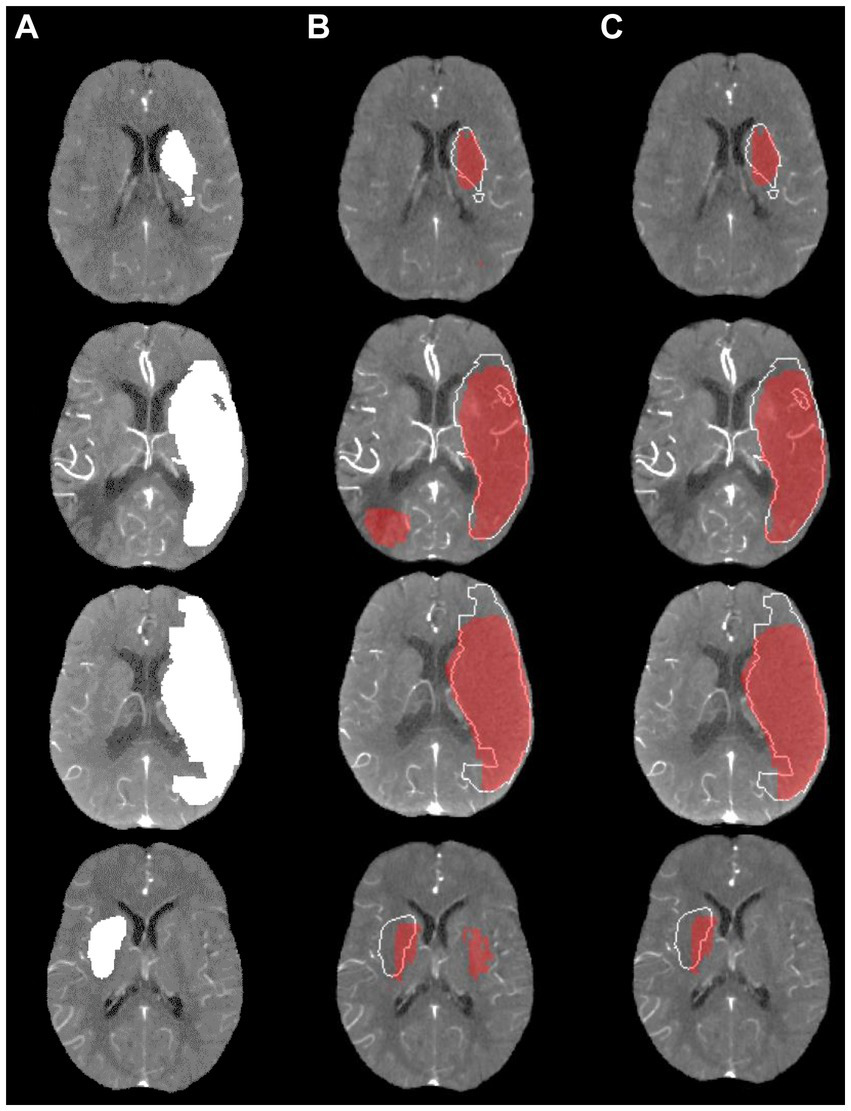

Figure 4 shows a visualization of the results obtained using the model with the highest average DSC compared to the ground truth for four exemplified patients. In these examples, the lesion was correctly located in all cases. However, the shape of predictions and ground truth do not fully align. It can be also seen that post-processing was primarily helpful to remove false lesions, especially those located in the contralateral hemisphere.

Figure 4

Visualization of lesion outcome prediction results obtained using the best model in terms of the average test set dice similarity coefficient for four exemplified patients. (A) Ground truth; (B) Prediction including small components red, ground truth white; (C) Prediction excluding small components red, ground truth white.